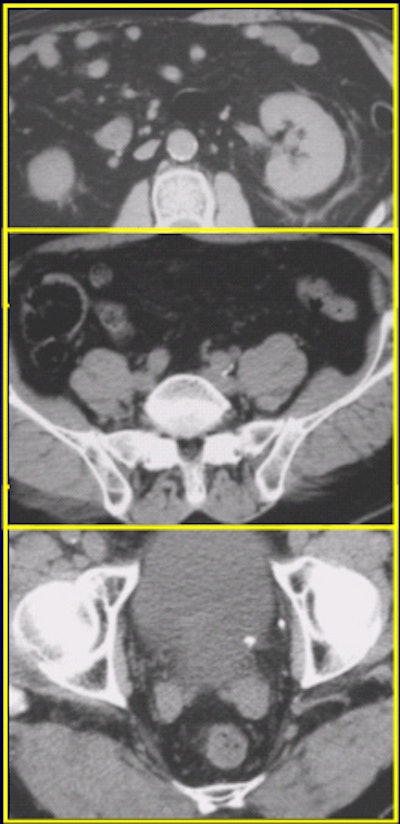

![]() |

Left ureterovesicle junction stone (UVJ) as seen on the 120-mAs CT scan above and on the 240-mAs scan below.